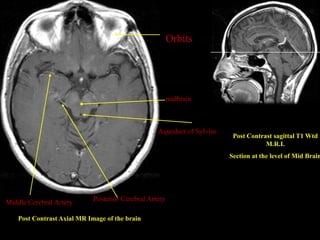

Orbits

midbrain

Aqueduct of Sylvius

Post Contrast sagittal T1 Wtd

M.R.I.

Section at the level of Mid Brain

Middle Cerebral Artery       Posterior Cerebral Artery

Post Contrast Axial MR Image of the brain

Orbits midbrain Aqueduct of Sylvius Post Contrast sagittal T1 Wtd M.R.I. Section at the level of Mid Brain Middle Cerebral Artery Posterior Cerebral Artery Post Contrast Axial MR Image of the brain